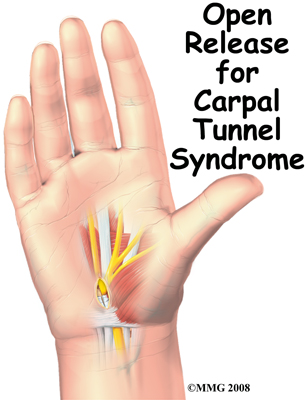

Open Carpal Tunnel Release

Carpal tunnel syndrome (CTS) occurs when the median nerve is squeezed as it courses through the wrist. The passageway through the wrist, called the carpal tunnel, is formed by the small wrist bones (carpals) on one side and a ligament on the other. In an open release for CTS, the surgeon makes an incision on the front of the wrist and hand in order to cut the ligament. The goal is to relieve pressure on the median nerve.